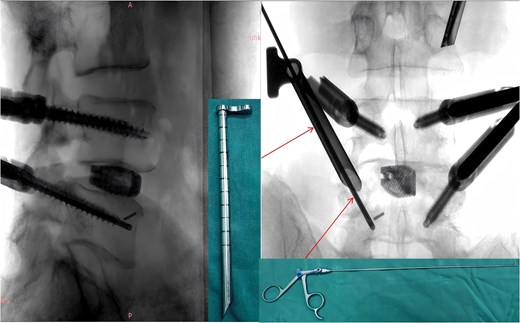

During the surgery, after sufficient decompression at the L4/L5 level and placement of the interbody fusion cage, a complication occurred during the percutaneous pedicle screw insertion. Intraoperative G-arm fluoroscopy confirmed the correct trajectory of the pedicle screw, established by the guidewire and puncture needle, and the pedicle screw was inserted along the established pathway (Fig. 2). However, after removing the guidewire, fluoroscopic imaging revealed that a portion of the guidewire had broken near the anterior margin of the left L5 pedicle screw (Fig. 3). The fracture likely occurred during screw insertion or tightening, which subsequently displaced the broken guidewire toward the anterior vertebral margin. Given the proximity of the fractured guide wire to the anterior vertebral margin, along with the risks of future migration causing injury to adjacent tissues or vessels, as well as the potential for local infection or pain, the decision was made to remove the fractured guidewire after obtaining informed consent from the patient’s legal representative.

Intraoperative fluoroscopic confirmation of guidewire breakage.